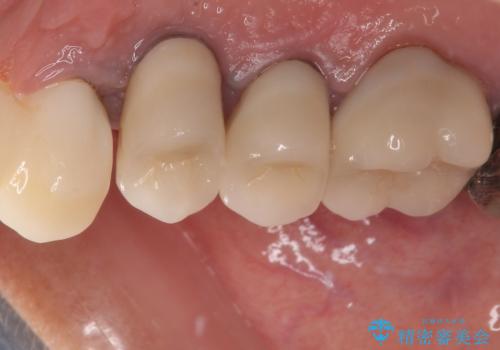

膿の出口が認められた頬側の歯槽骨は欠損が大きかったものの、インプラント埋入には十分な骨があり、無事に短期間で治療を終えることができました。